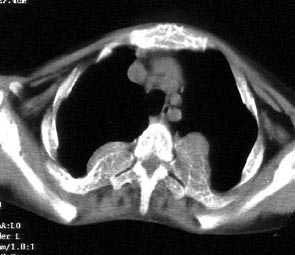

以下是引用jiajie在2004-12-10 22:14:53的发言:[br]多发性肋骨骨质疏松,[br][br]麦粒状及筛孔状骨质破坏,[br][br]髓腔膨胀皮质变薄,[br][br]骨旁多发软组织肿块,[br][br]考虑恶性病变,支持肋骨多发性骨髓瘤。

以下是引用pujunzhi在2008-7-3 21:21:00的发言:[br]支持地中海贫血伴髓外造血可能性大,需与多发性骨髓瘤、淋巴瘤等鉴别。